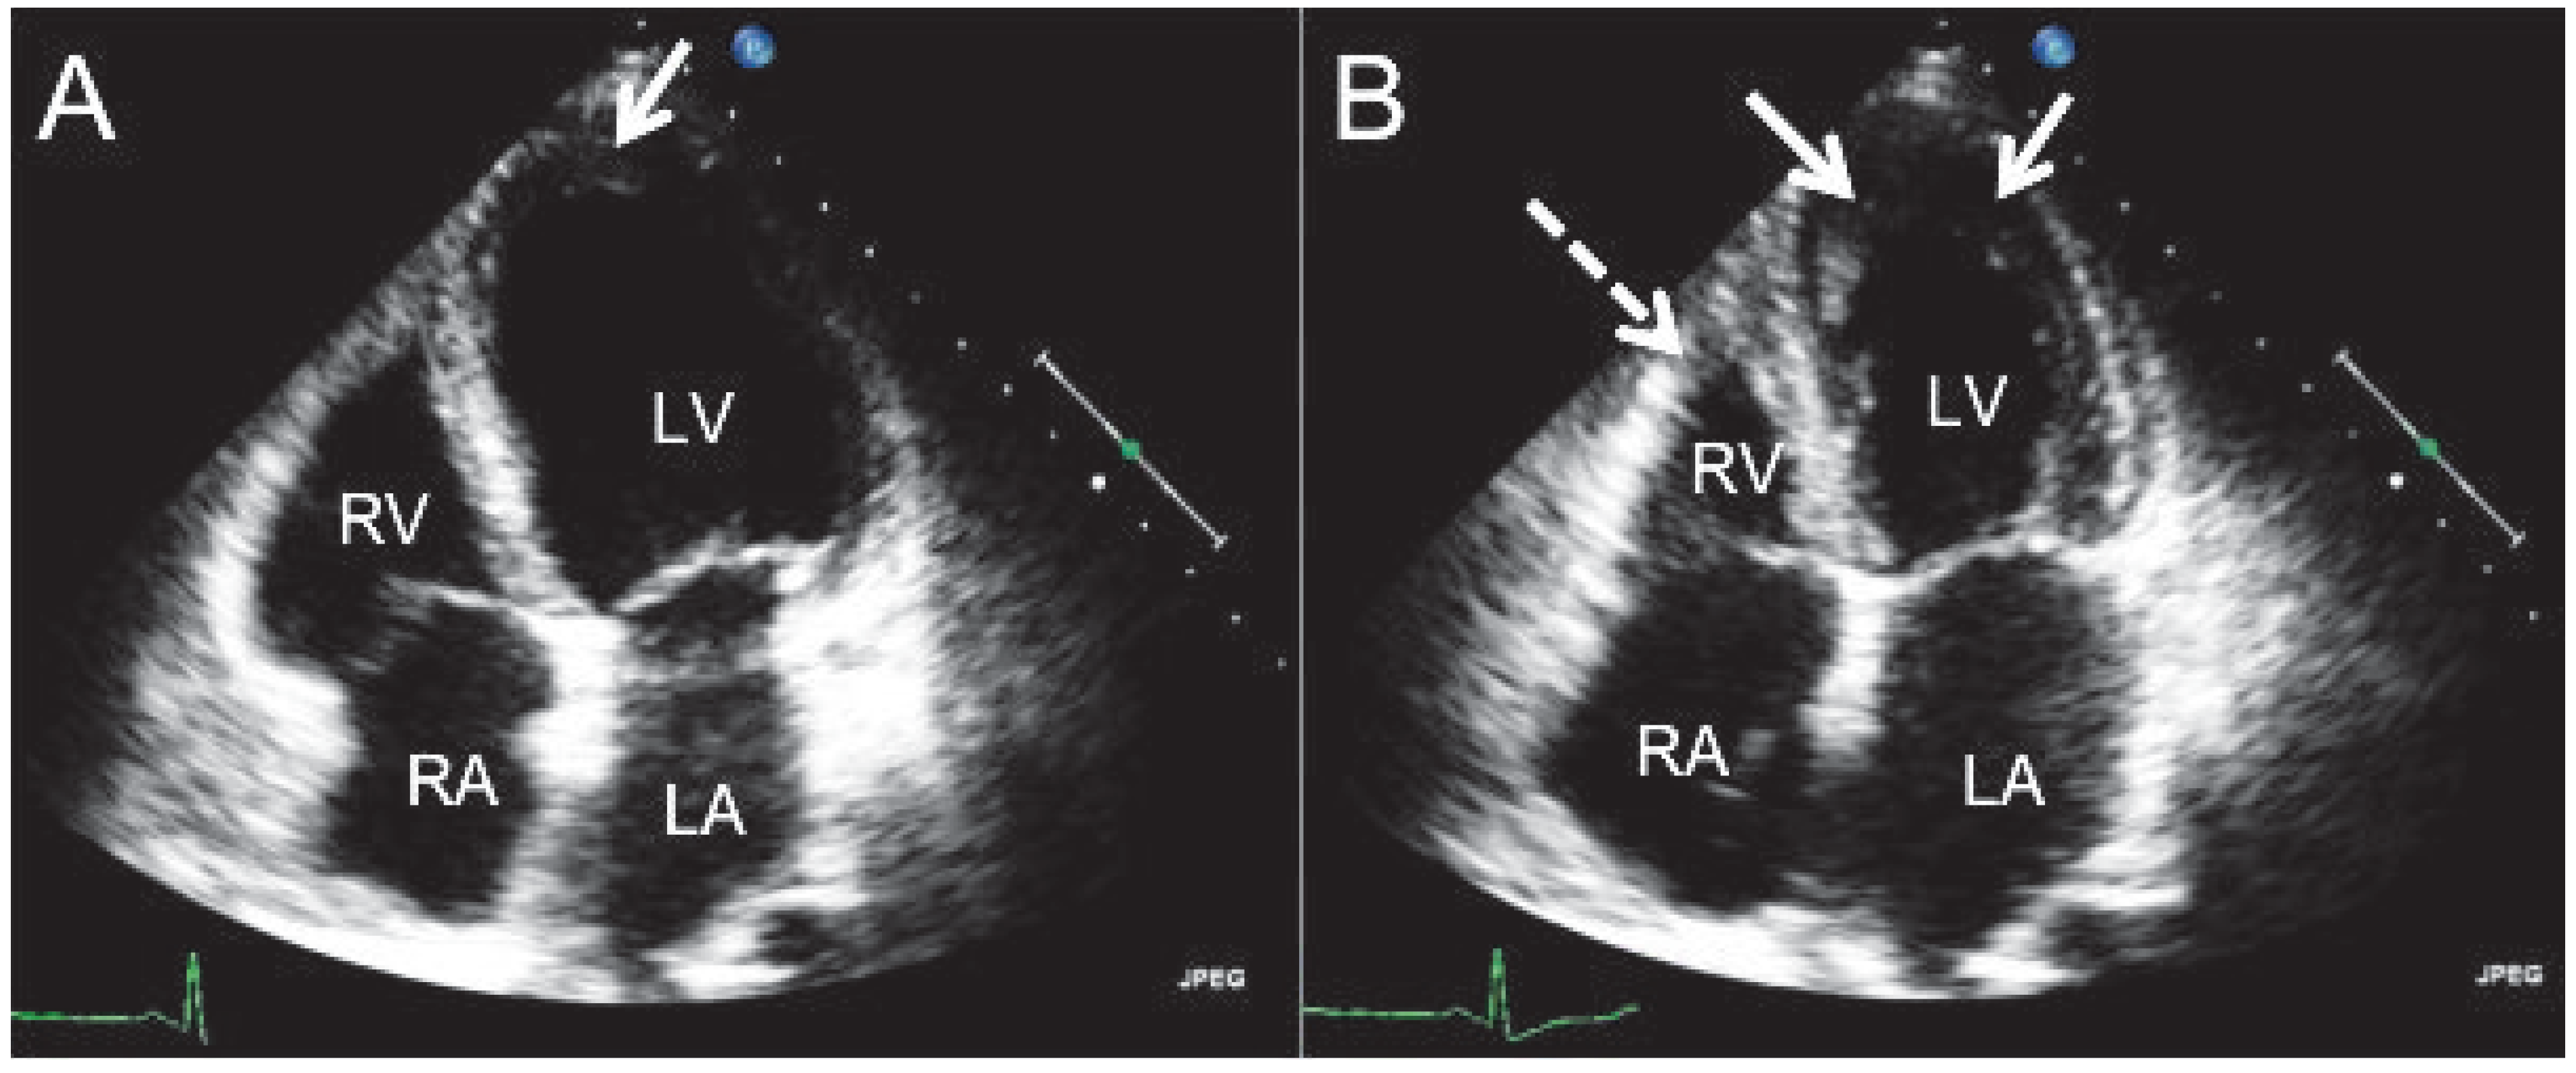

Laboratory tests showed an elevated NTpro-BNP level (4280 ng/l) and the white blood cell count revealed transient hypereosinophilia (Table 1). Immunological testing revealed unspecifically elevated ANA of 1:80. The antineutrophil cytoplasmatic antibodies (ANCA) were negative. Only immunoglobulin E (IgE) was positive (187 kU/l). Echocardiography suggested endomyocardial fibrosis with involvement of both chambers (Figure 1). A mural apposition thrombus could be detected on the apical wall segment and the inferior midventricular wall segment with hypokinesia. Left ventricular ejection fraction was preserved (60%). Mitral inflow pattern and pulmonary vein flow variables suggested first grade diastolic dysfunction. The right ventricle showed only apical involvement. A small pericardial effusion without any haemodynamic relevance was noted. The mitral valve leaflets were normal, but the chordae tendineae were thickened.

Figure 1.

The transthoracic apical 4-chamber view shows endomyocardial fibrosis in enddiastole (A) and endsystole (B). The apposition is on the apical wall segment and the inferior midventricular wall segment of the left ventricle (arrows). The right ventricle shows apical involvement (broken arrow). RA = right atrium; RV = right ventricle; LA = left atrium; LV = left ventricle.